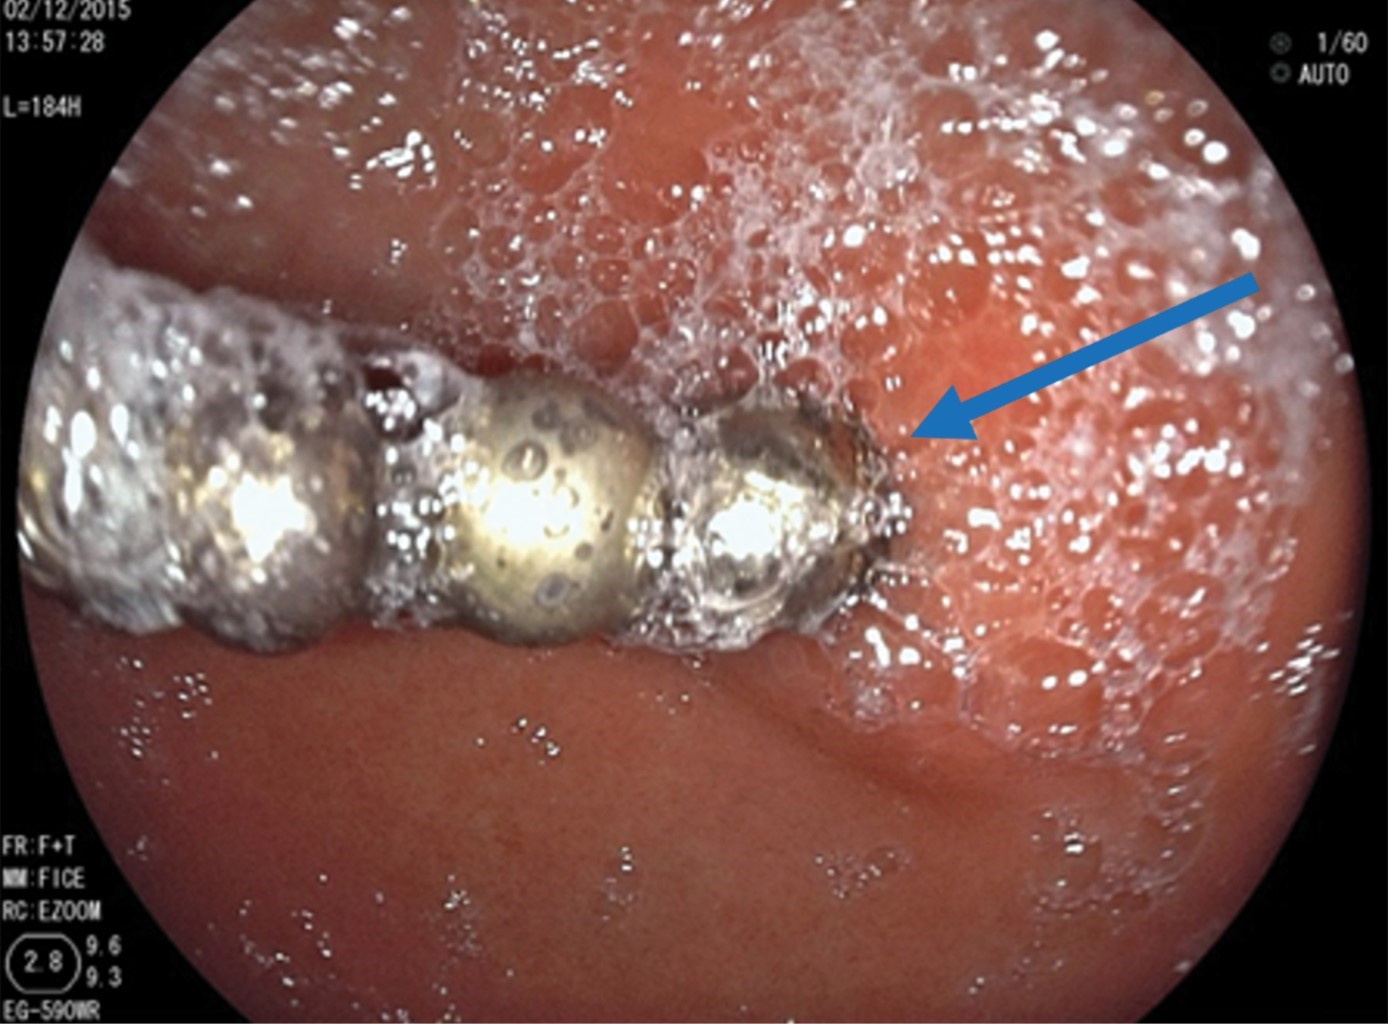

Se realiza endoscopía alta con equipo rígido en el que se aprecian tres imanes en la faringe que se extraen con pinza de caimán. Posteriormente, se efectúa panendoscopía, donde se observa esófago sin alteraciones. En estómago, a nivel del antro, se observaron ocho imanes que se extraen con red atrapa pólipos (Figura 3). Se identifica una úlcera de 4 mm con bordes congestivos y edematosos, en su interior se encuentra un imán incrustado (Figura 4). En el duodeno no se identifican lesiones.

Figura 3